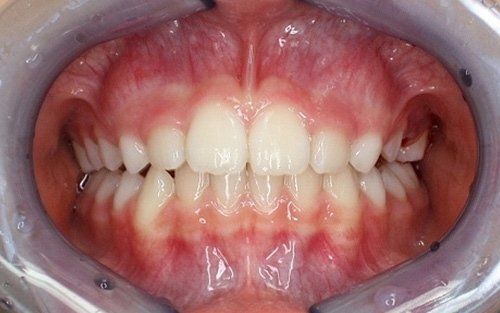

Prevede trattamenti in età precoce, tra i 7 e i 10 anni, durante gli stadi più attivi della crescita cranio facciale e della permuta dentale. Tali interventi sono finalizzati a rimuovere i fattori responsabili della malocclusione dentaria e a ripristinare la normale crescita dei mascellari rendendo possibile un allineamento dentale corretto, estetico e funzionale.

L’ortodonzia intercettiva, può non portare a una risoluzione completa della malocclusione, ma pone solide basi per una crescita più armonica del complesso dento-scheletrico, diminuendo la gravità del problema e rendendo l’eventuale fase terapeutica successiva più semplice, più breve e più sopportabile per il paziente in crescita.Trattare preventivamente le malocclusioni intercettandole al momento giusto, molto spesso evita, nel futuro, scelte più drastiche ed invasive come le estrazioni dentarie o soluzioni chirurgiche ortodontiche a fine crescita.